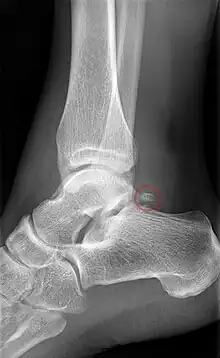

Talus injuries may be difficult to recognize,[9][10] and lateral process fractures in particular may be radiographically occult. If not recognized and managed appropriately, a talus fracture may result in complications and long-term morbidity. A 2015 review came to the conclusion that isolated talar body fractures may be more common than previously thought.[4]

A fractured talar body often has a displacement that is best visualised using CT imaging. In case a talus fracture is accompanied by a dislocation, restoration of articular and axial alignment is necessary to optimize ankle and hindfoot function.[9]